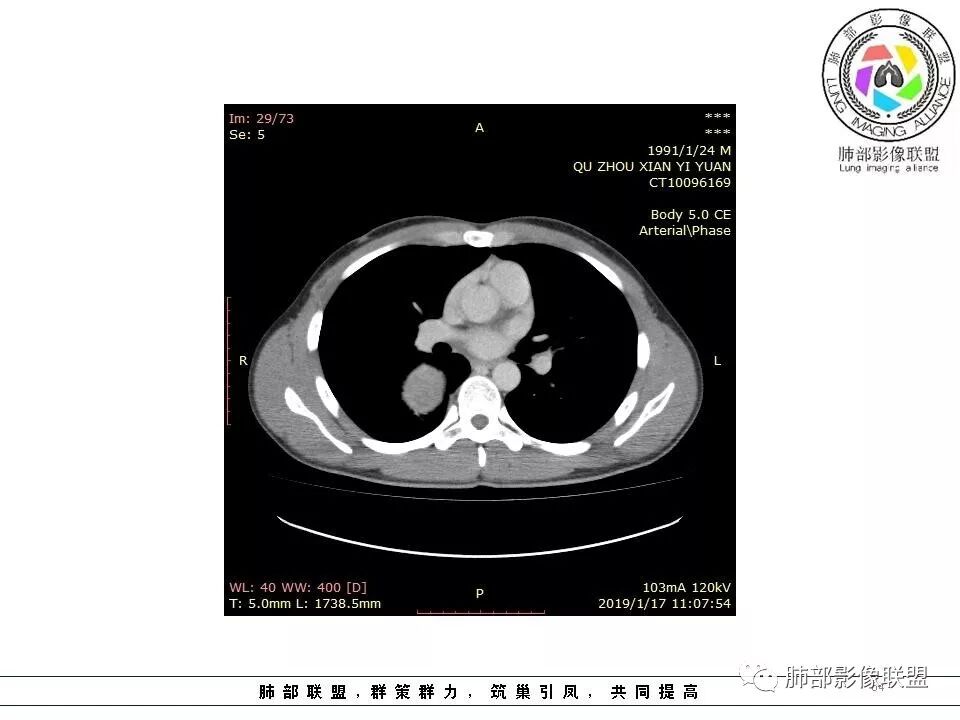

右后纵膈脊柱旁软组织占位,形态规则类圆,边缘光整,肺组织受压,胸膜尾,肋间动脉供血。中度不均匀延迟强化。

后纵隔脊柱旁占位性病变,疾病谱有神经鞘瘤,sft,节细胞瘤,髓外造血。此例有胸膜尾征,蛇纹征 ,延迟强化。考虑胸膜孤立性纤维瘤。看到有供血动脉,但不知道是哪里的血管。

右后纵膈脊柱旁软组织影,与纵隔结构分界不清,形态规则类圆,边缘光整,肺组织受压,胸膜尾,肋间动脉供血。肺动脉推移,中度不均匀延迟强化。考虑神经来源,神经鞘瘤,神经纤维瘤二者不易鉴别。

病灶定位脏层胸膜,肺组织受挤压,有胸膜尾征,动脉期可见血管支配,考虑肺动脉供血,静脉期,强化增强明显,符合快进慢出特点,病灶内可见低密度区,考虑胸膜孤立纤维瘤。

青年男性,右侧脊柱旁软组织肿块,边缘膨隆,密度不均,临近肺组织受压、胸膜增厚,增强后动脉期呈不均匀强化,并可见肋间动脉供血,延迟期强化较均匀,定位肺外,首先考虑SFT,神经源性肿瘤待排

右肺占位,跨越上叶后段、下叶背,边缘光滑,瘤肺界面清,见肺压缩缘(线样不张`强化),见胸膜尾征,胸膜下脂肪未见明显增厚,肋骨丶脊柱未见侵袭及受压,渐进性丶地图样强化,冠状位似见体循环供血

右后纵膈肿块,肺瘤界面清楚,胸膜尾征,邻近肺组织及支气管被推移,部分脂肪间隙存在,定位肺外来源,血供来自肋间动脉,增强后持续渐进强化,蛇纹征,考虑SFT,鞘瘤肿块内血管罕见,不考虑。

右上肺野脊柱旁软组织肿块,边缘光滑整齐,肺组织及气管右肺上叶支气管受压前移,外移,边缘可见胸膜尾征,病灶内密度不均,增强后渐进性持续强化,其内可见明显蛇纹血管征,首先考虑肺外来源,sft.可能性大

肋间动脉供血,强化尚均匀,逐步强化

2.肋间动脉病供血也提示肿块来自后纵隔?

3.相邻椎间孔未见扩大,也未见块影延入椎管,易起自于神经根的鞘瘤似乎找不到支持点。

可惜未提供矢状位骨窗图像,如在肋骨内下缘观察到压迹有助于肋间神经的鞘瘤的判断,这是因为二者之间密切的毗邻关系。

4.静脉期轻度不均匀强化,注意不是环形强化,亦未见明确的“AB区”,这点也不支持神经鞘瘤。临床及病灶轻度强化都不支持副节瘤。